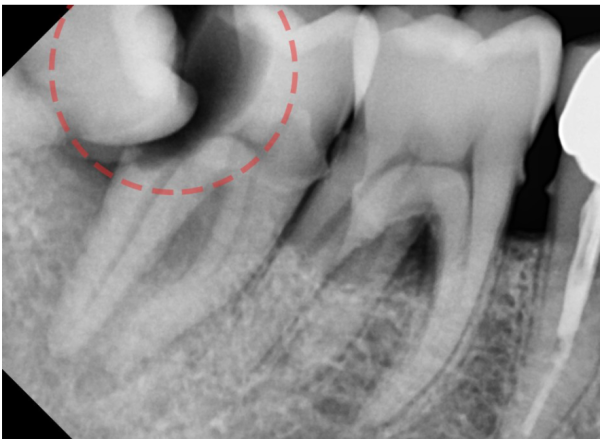

이 환자분은 어금니쪽에 통증이 있다고 하셔서

수진동치과 더서울치과를 찾아오셨습니다.

정확히 진단을 하기 위하여 엑스레이로 확인을 했는데요.

사랑니가 이렇게 누워있었습니다.

This patient has pain in her molars

You are here at Soojin-dong Dental Clinic The Seoul Dental Clinic.

I checked with an X-ray to make an accurate diagnosis.

My wisdom tooth was lying down like this.

조금더 확대한 사진을 보면 누워있는 사랑니와

바로 앞에 인접한 어금니 사이에 충치가 생겨서 상당히 통증이 느껴질법한 상태였습니다.